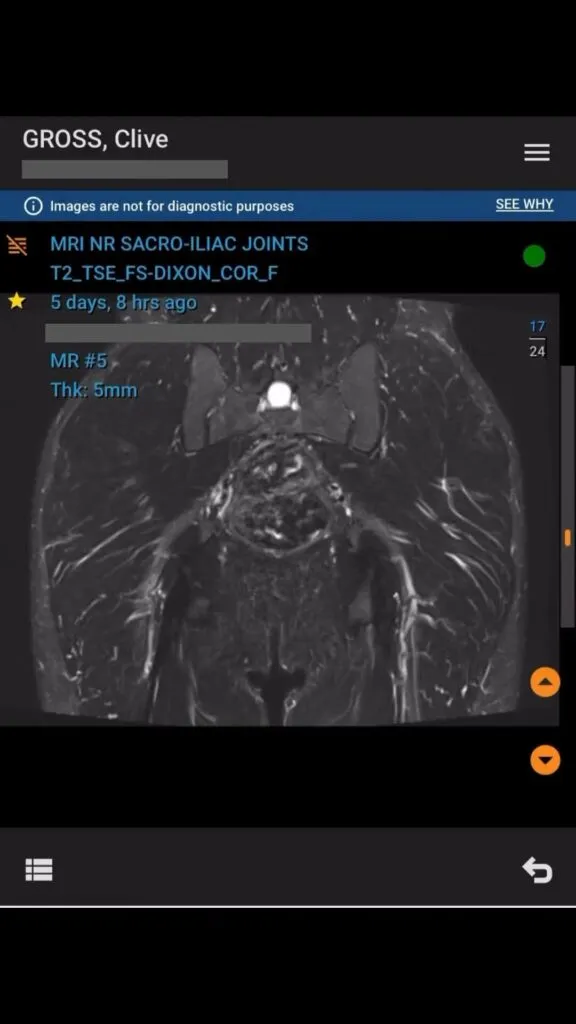

Week 5 has been a tough one. I’ve been dealing with what feels like another sacral stress fracture, a familiar challenge for me. Thankfully, the MRI showed no bone stress injury, but I’m still closely monitoring my recovery and adjusting my training plan to stay on track for the marathon.